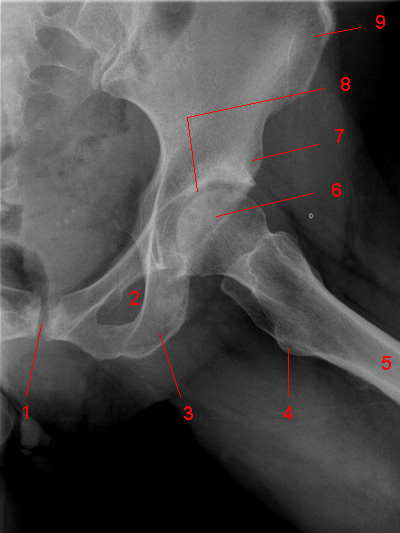

Для своевременного выявления ранних проявлений коксартроза нами применяется комплексный подход в диагностике данной патологии, включающий: опрос, осмотр сустава, проверка объема движения в нем, рентгенографию, компьютерную томографию (КТ), магнитно-резонансную томографию (МРТ) и ультразвуковое исследование (УЗИ) тазобедренного сустава.

На рентгенограммах тазобедренный сустав сохраняет нормальную форму, суставная щель умеренно или неравномерно сужена с субхондральным склерозированием костных суставных поверхностей, непостоянными краевыми костными разрастаниями (I стадия).

Рентгенологически суставная щель может быть равномерно или неравномерно сужена, ацетабулярная суставная впадина уплощена, присутствуют явления субхондрального склероза, краевые костные разрастания. Конфигурация головки бедренной кости, как правило, не нарушена (II стадия).

В подавляющем большинстве случаев диагноз коксартроза ставится при рентгенографии, где видны изменения формы и структуры костей, составляющих тазобедренный сустав. Однако рентгенографически в ряде случаев затруднительно зафиксировать ранние проявления артроза, так как хрящевая ткань суставных поверхностей на рентгеновских снимках не отображается и мы можем судить о дегенеративном процессе, когда он достаточно выражен, вызывая изменения ширины просвета рентгеновской суставной щели.

КТ тазобедренного сустава проведено с 2002 года в 80, МРТ с 2011 года — в 22 случаях. Предпочтение следует отдать МРТ, так как при данном виде исследования можно четко визуализировать суставную капсулу и связки, идентифицировать даже поверхностные изменения хрящевого слоя, а также мелкие очаги субкортикального трабекулярного отека губчатого вещества костной ткани. КТ позволяет оценить минимальные изменения структуры и формы костной ткани, однако в общем объеме получаемой информации уступая МРТ в информативности. При углубленном обследовании для уточнения диагноза «коксартроз» и степени его выраженности можно рекомендовать проведение именно МРТ тазобедренных суставов.

Предпочтение следует отдать МРТ, так как при данном виде исследования можно четко визуализировать суставную капсулу и связки, идентифицировать даже поверхностные изменения хрящевого слоя, а также мелкие очаги субкортикального трабекулярного отека губчатого вещества костной ткани. КТ позволяет оценить минимальные изменения структуры и формы костной ткани, однако в общем объеме получаемой информации уступая МРТ в информативности. При углубленном обследовании для уточнения диагноза «коксартроз» и степени его выраженности можно рекомендовать проведение именно МРТ тазобедренных суставов.

На ранних стадиях диагностировать артроз можно только при проведении КТ или МРТ.

Выводы. Таким образом, учитывая доступность и экономическую целесообразность, скрининговыми методами диагностики коксартроза являются рентгенография и УЗИ тазобедренных суставов. При несоответствии клинической картины и данных методов исследования необходимо КТ и (или) МРТ, что позволяет повысить качество диагностики и назначить адекватную терапию.